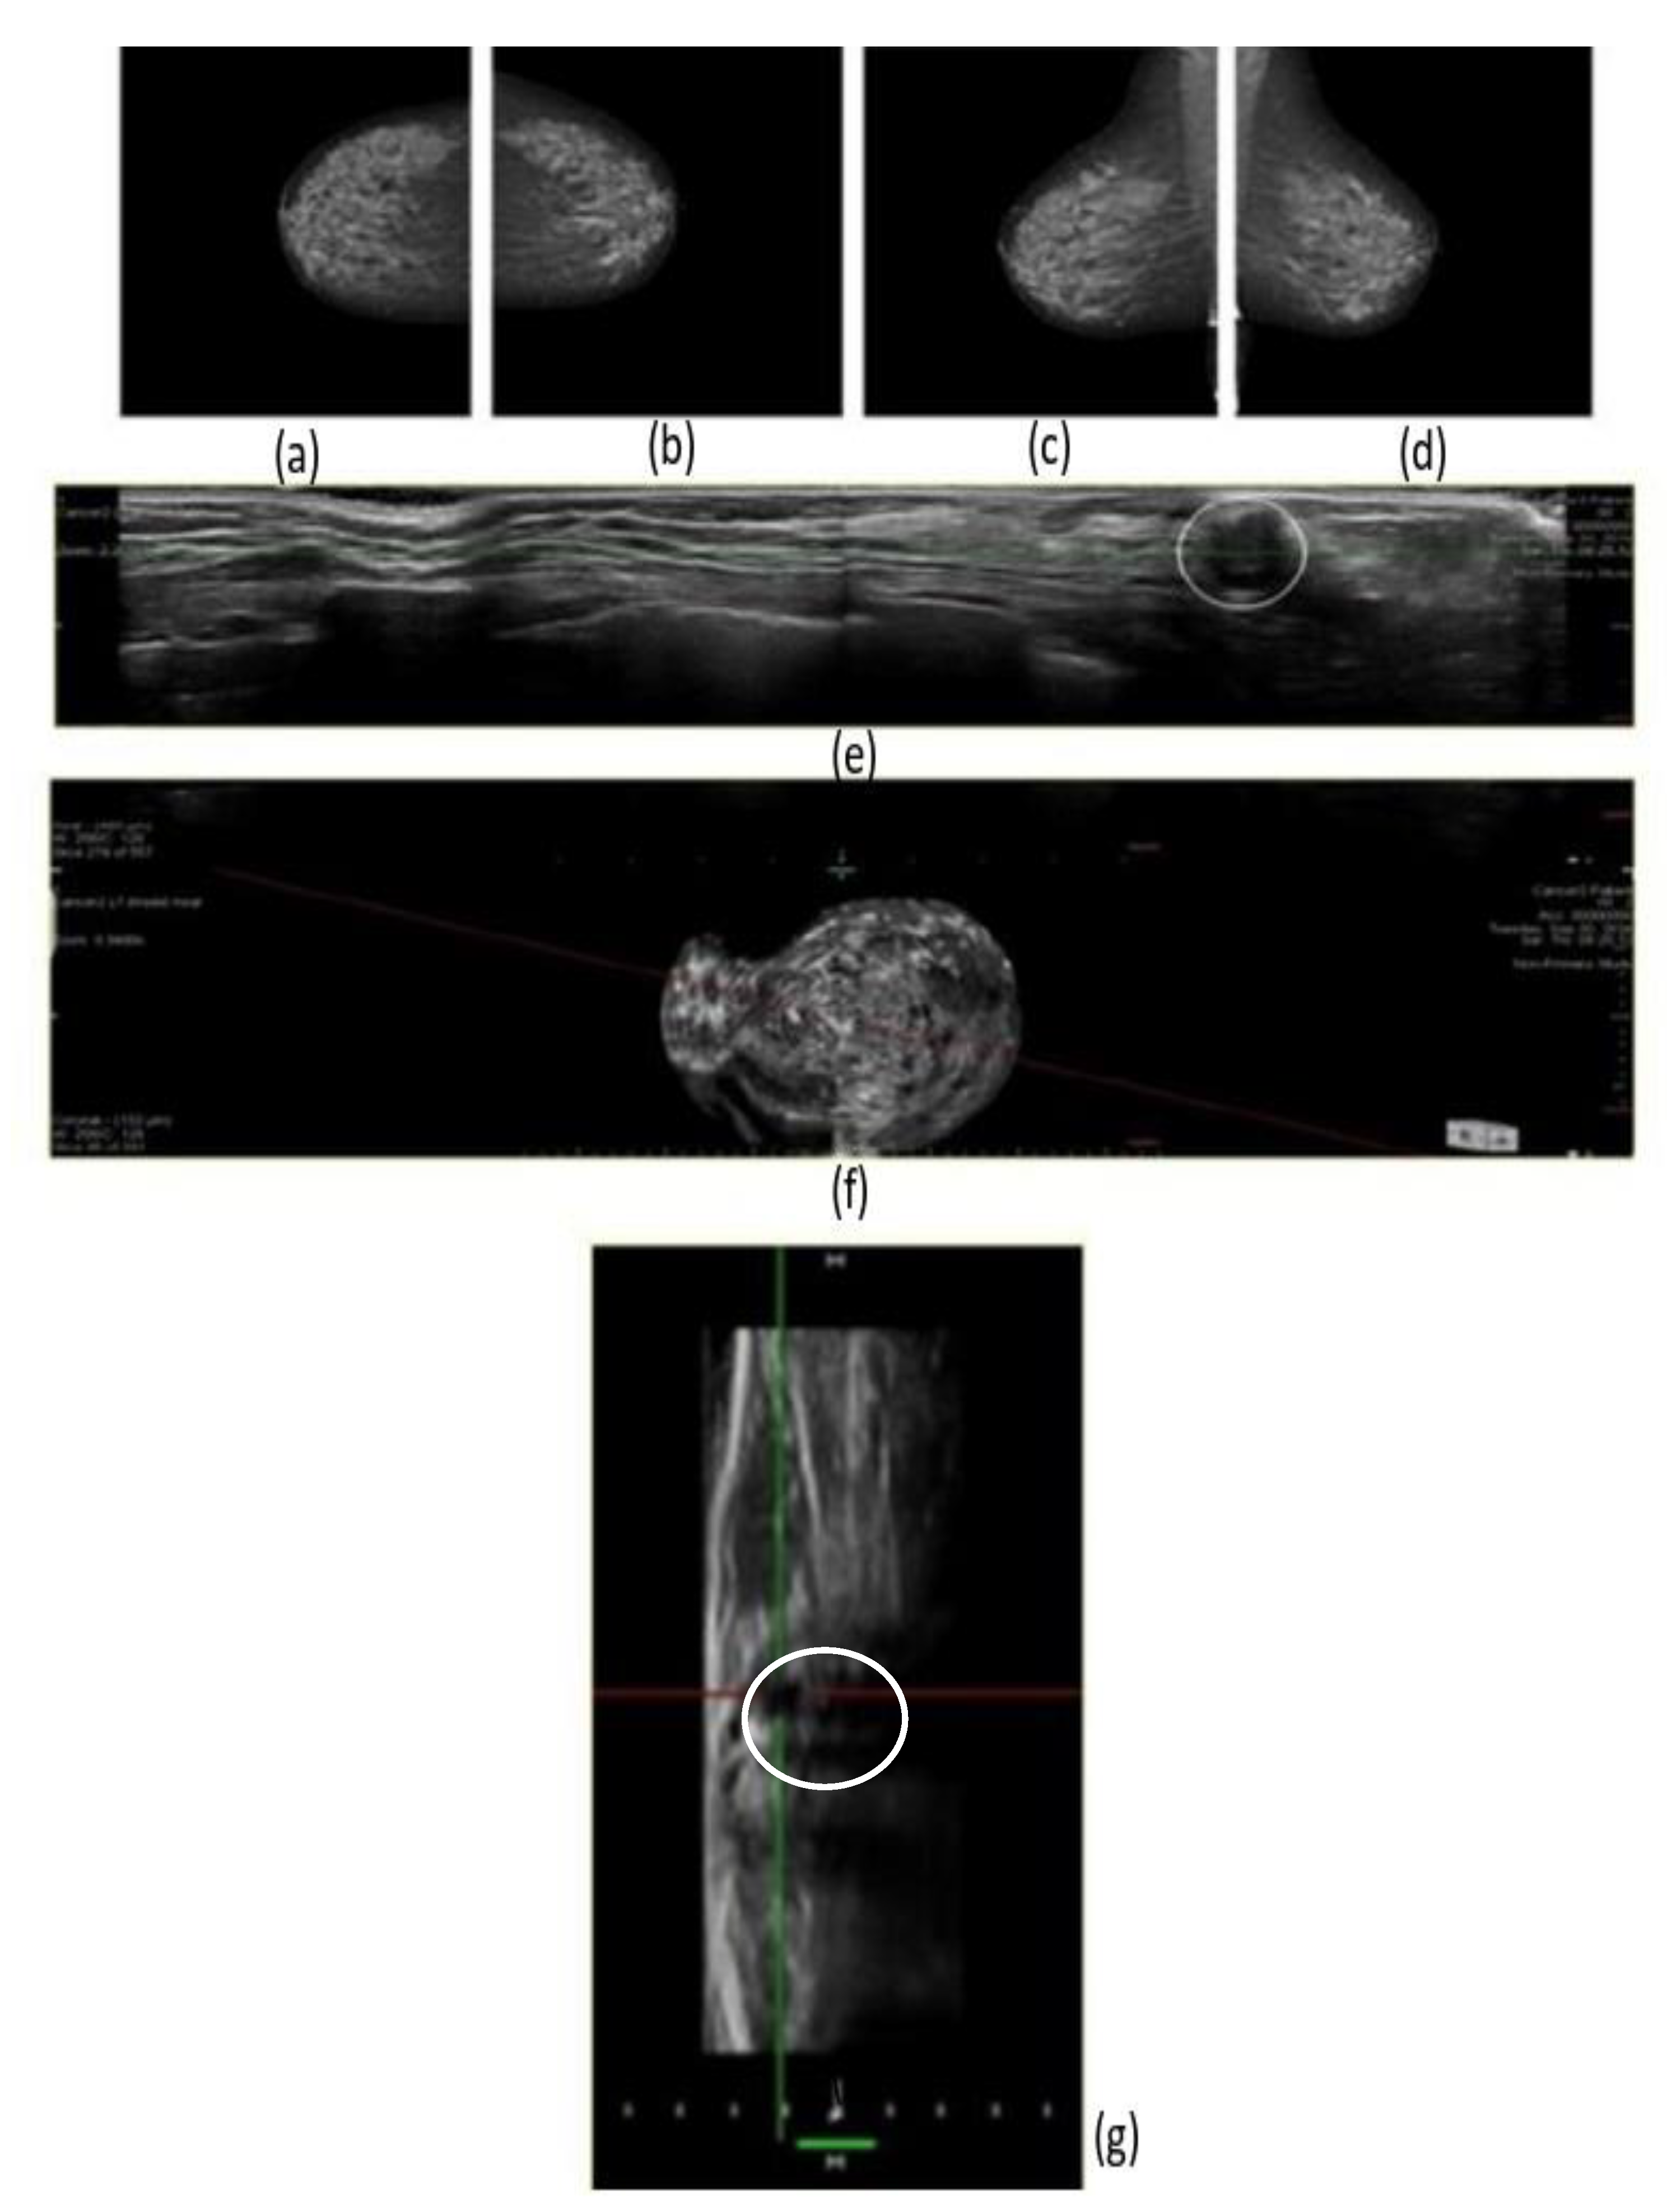

2.2. FFDM

2.3. 3D Prone ABUS

2.4. Interpretation of Images